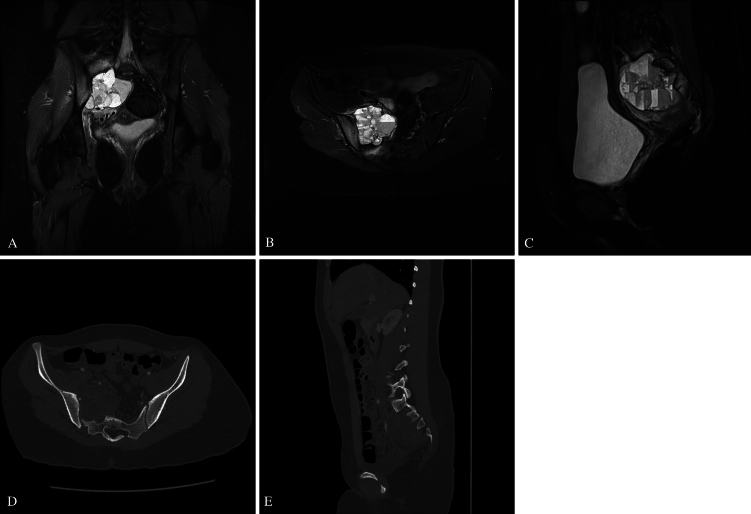

Observations: A 15-year-old girl presented with a 3-month history of right S1-2 radicular pain and right dorsiflexion and plantar flexion weakness. Imaging revealed a right sacral alar aneurysmal bone cyst. The patient underwent right S1-3 hemilaminectomies and partial resection of the S2 and S3 vertebral bodies. Following adequate bony decompression, tumor debulking was performed. Bilateral L4-S1 pedicle screws and left S2AI screws were then placed using neuronavigation guidance. Due to right S1-2 sacral resection, S2AI screw placement was unfeasible. Right-S3 alar-iliac (S3AI) screw placement was performed, and good sacropelvic fixation was demonstrated. Herein, the authors describe the first clinical application of S3AI screw placement in a pediatric patient. After surgery, the patient experienced an improvement in symptoms before later tumor recurrence, which required adjuvant therapy. Long term follow-up revealed solid fusion with stable spinal alignment.

Lessons: In select patients in whom S2AI screw placement is not an option, S3AI screw placement is a feasible, safe, alternative for sacropelvic fixation. https://thejns.org/doi/10.3171/CASE25267.